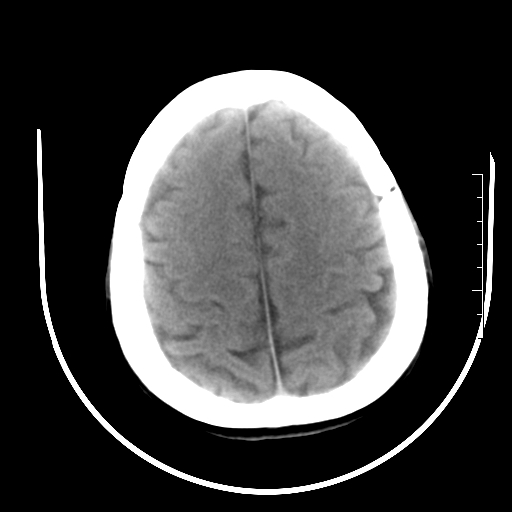

标题: CT27880:f、55y,头痛。 [打印本页]

标题: CT27880:f、55y,头痛。

考虑左侧顶部镰旁脑膜瘤;建议行ct增强扫描检查。

考虑左侧顶部镰旁脑膜瘤,建议行ct增强扫描检查。

考虑左侧顶部镰旁脑膜瘤;建议行ct增强扫描检查

大脑镰旁脑膜瘤可能,建议增强或mri

左侧顶部镰旁脑膜瘤,增强